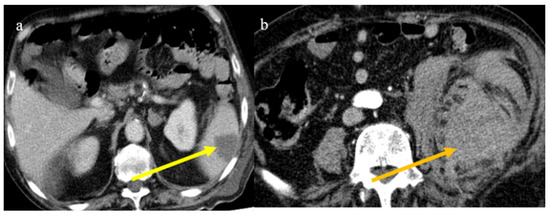

- Bonaffini, P.A.; Franco, P.N.; Bonanomi, A.; Giaccherini, C.; Valle, C.; Marra, P.; Norsa, L.; Marchetti, M.; Falanga, A.; Sironi, S. Ischemic and hemorrhagic abdominal complications in COVID-19 patients: Experience from the first Italian wave. Eur. J. Med. Res. 2022, 27, 1–9. [Google Scholar] [CrossRef]

- Peshevska-Sekulovska, M.; Boeva, I.; Sekulovski, M.; Zashev, M.; Peruhova, M. Gastrointestinal Ischemia—Stumbling Stone in COVID-19 Patients. Gastroenterol. Insights 2022, 13, 206–217. [Google Scholar] [CrossRef]

- Norsa, L.; Bonaffini, P.A.; Caldato, M.; Bonifacio, C.; Sonzogni, A.; Indriolo, A.; Valle, C.; Furfaro, F.; Bonanomi, A.; Franco, P.N.; et al. Intestinal ischemic manifestations of SARS-CoV-2: Results from the ABDOCOVID multicentre study. World J. Gastroenterol. 2021, 27, 5448–5459. [Google Scholar] [CrossRef]

- Caruso, D.; Zerunian, M.; Pucciarelli, F.; Lucertini, E.; Bracci, B.; Polidori, T.; Guido, G.; Polici, M.; Rucci, C.; Iannicelli, E.; et al. Imaging of abdominal of abdominal complications of COVID-19 infection. BJR Open 2021, 2, 20200052. [Google Scholar] [CrossRef]

- Ojha, V.; Mani, A.; Mukherjee, A.; Kumar, S.; Jagia, P. Mesenteric ischemia in patients with COVID-19: An updated systematic review of abdominal CT findings in 75 patients. Abdom. Imaging 2021, 47, 1565–1602. [Google Scholar] [CrossRef]

- Boraschi, P.; Giugliano, L.; Mercogliano, G.; Donati, F.; Romano, S.; Neri, E. Abdominal and gastrointestinal manifestations in COVID-19 patients: Is imaging useful? World J. Gastroenterol. 2021, 27, 4143–4159. [Google Scholar] [CrossRef]

- Keshavarz, P.; Rafiee, F.; Kavandi, H.; Goudarzi, S.; Heidari, F.; Gholamrezanezhad, A. Ischemic gastrointestinal complications of COVID-19: A systematic review on imaging presentation. Clin. Imaging 2020, 73, 86–95. [Google Scholar] [CrossRef] [PubMed]